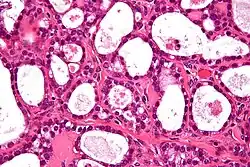

Micrograph of an ovarian clear-cell carcinoma. H&E stain

Ovarian clear-cell carcinoma often occurs as a pelvic mass that rarely appears bilaterally. The cells usually contain glycogen with large clear cytoplasm. It is also associated with endometriosis, a disorder of abnormal tissue growth outside of the uterus.[3] The tumor cells emerge in a stepwise manner from adenofibromas which are benign endometriotic cysts. They also hold molecular genetic mutations in both ARID1A and PIK3CA, similar to other epithelial ovarian cancers. Mutations in ARID1A commonly contain phosphatase and tensin homolog (PTEN) that are hypothesized to contribute to clear-cell tumorigenesis. However, research also shows that inactivation of ARID1A alone does not lead to tumor initiation. However, clear-cell tumors rarely carry p53, BRCA1, or BRCA2 mutations.[4] In addition, they also test negative for estrogen and progesterone receptors and Wilm tumor suppressor 1.[5] Studies have also suggested that clear-cell carcinoma can occur with thromboembolic complications and hypercalcemia. Recurrence of tumor cells have been reported to involve lymph nodes and parenchymal organs.